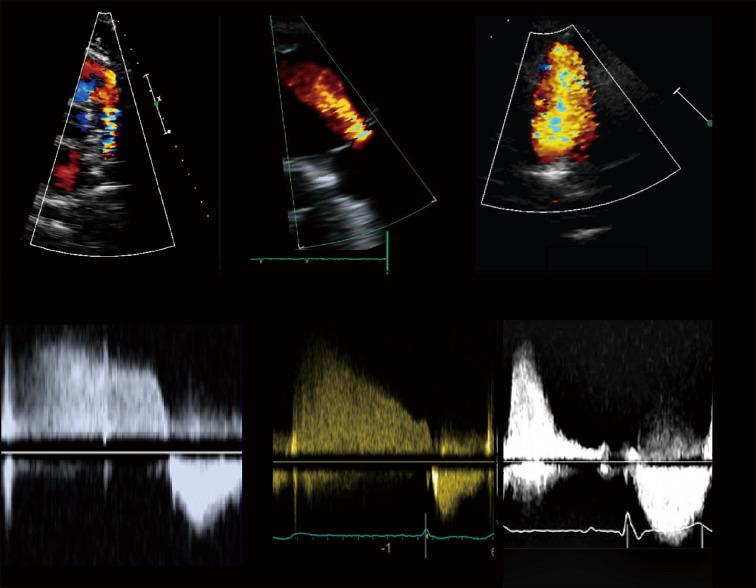

Thanks to advances in pediatric cardiology, most infants with tetralogy of Fallot (TOF) now survive into adulthood. This relatively new population of adult patients may face long-term complications, including pulmonary regurgitation (PR), right ventricular (RV) tract obstruction, residual shunts, RV dysfunction, and arrythmias. They will often need to undergo pulmonary valve (PV) replacement and other invasive re-interventions. However, the optimal timing for these procedures is challenging, largely due to the complexity of evaluating RV volume and function. The options for the follow-up of these patients have rapidly evolved from an angiography-based approach to the surge of advanced imaging techniques, mainly echocardiography, cardiac magnetic resonance (CMR), and computer tomography (CT). In this review, we outline the indications, strengths and limitations of these modalities in the adult TOF population.